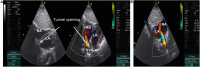

Introduction: Congenital descending aorta-right atrial tunnel is a rare congenital heart defect. Herein, a new case successfully treated by transcatheter closure using a new type of ventricular septal defect occluder from the aortic side was reported. Case Presentation: An 11-month-old Chinese girl presenting with a cardiac murmur was suspected with partial anomalous pulmonary venous connection as assessed by echocardiography. Descending aorta-right atrial tunnel was confirmed by computed tomography angiography and cardiac catheterization. Subsequently, transcatheter closure was performed successfully using a new type of ventricular septal defect occluder from the aortic side. The cardiac murmur disappeared after the intervention, and echocardiography did not reveal any abnormal flow inside the right atrium. At 6 months, the patient had no murmur, and no residual shunt was found using the echocardiogram. Conclusion: Descending aorta-right atrial tunnel is a rare anomaly. Transcatheter closure was successful in our case. Long-term follow-up is needed to assess any progressive growth of the residual tunnel.